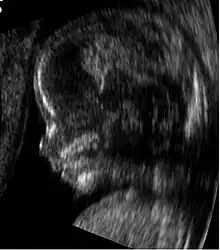

Obstetric ultrasonography showing a fetus at 14 weeks of gestational age, through the median plane.